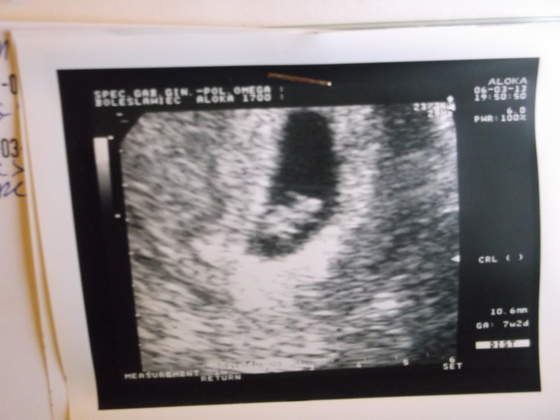

dołączam fotkę i pozdrawiam wszystkie!